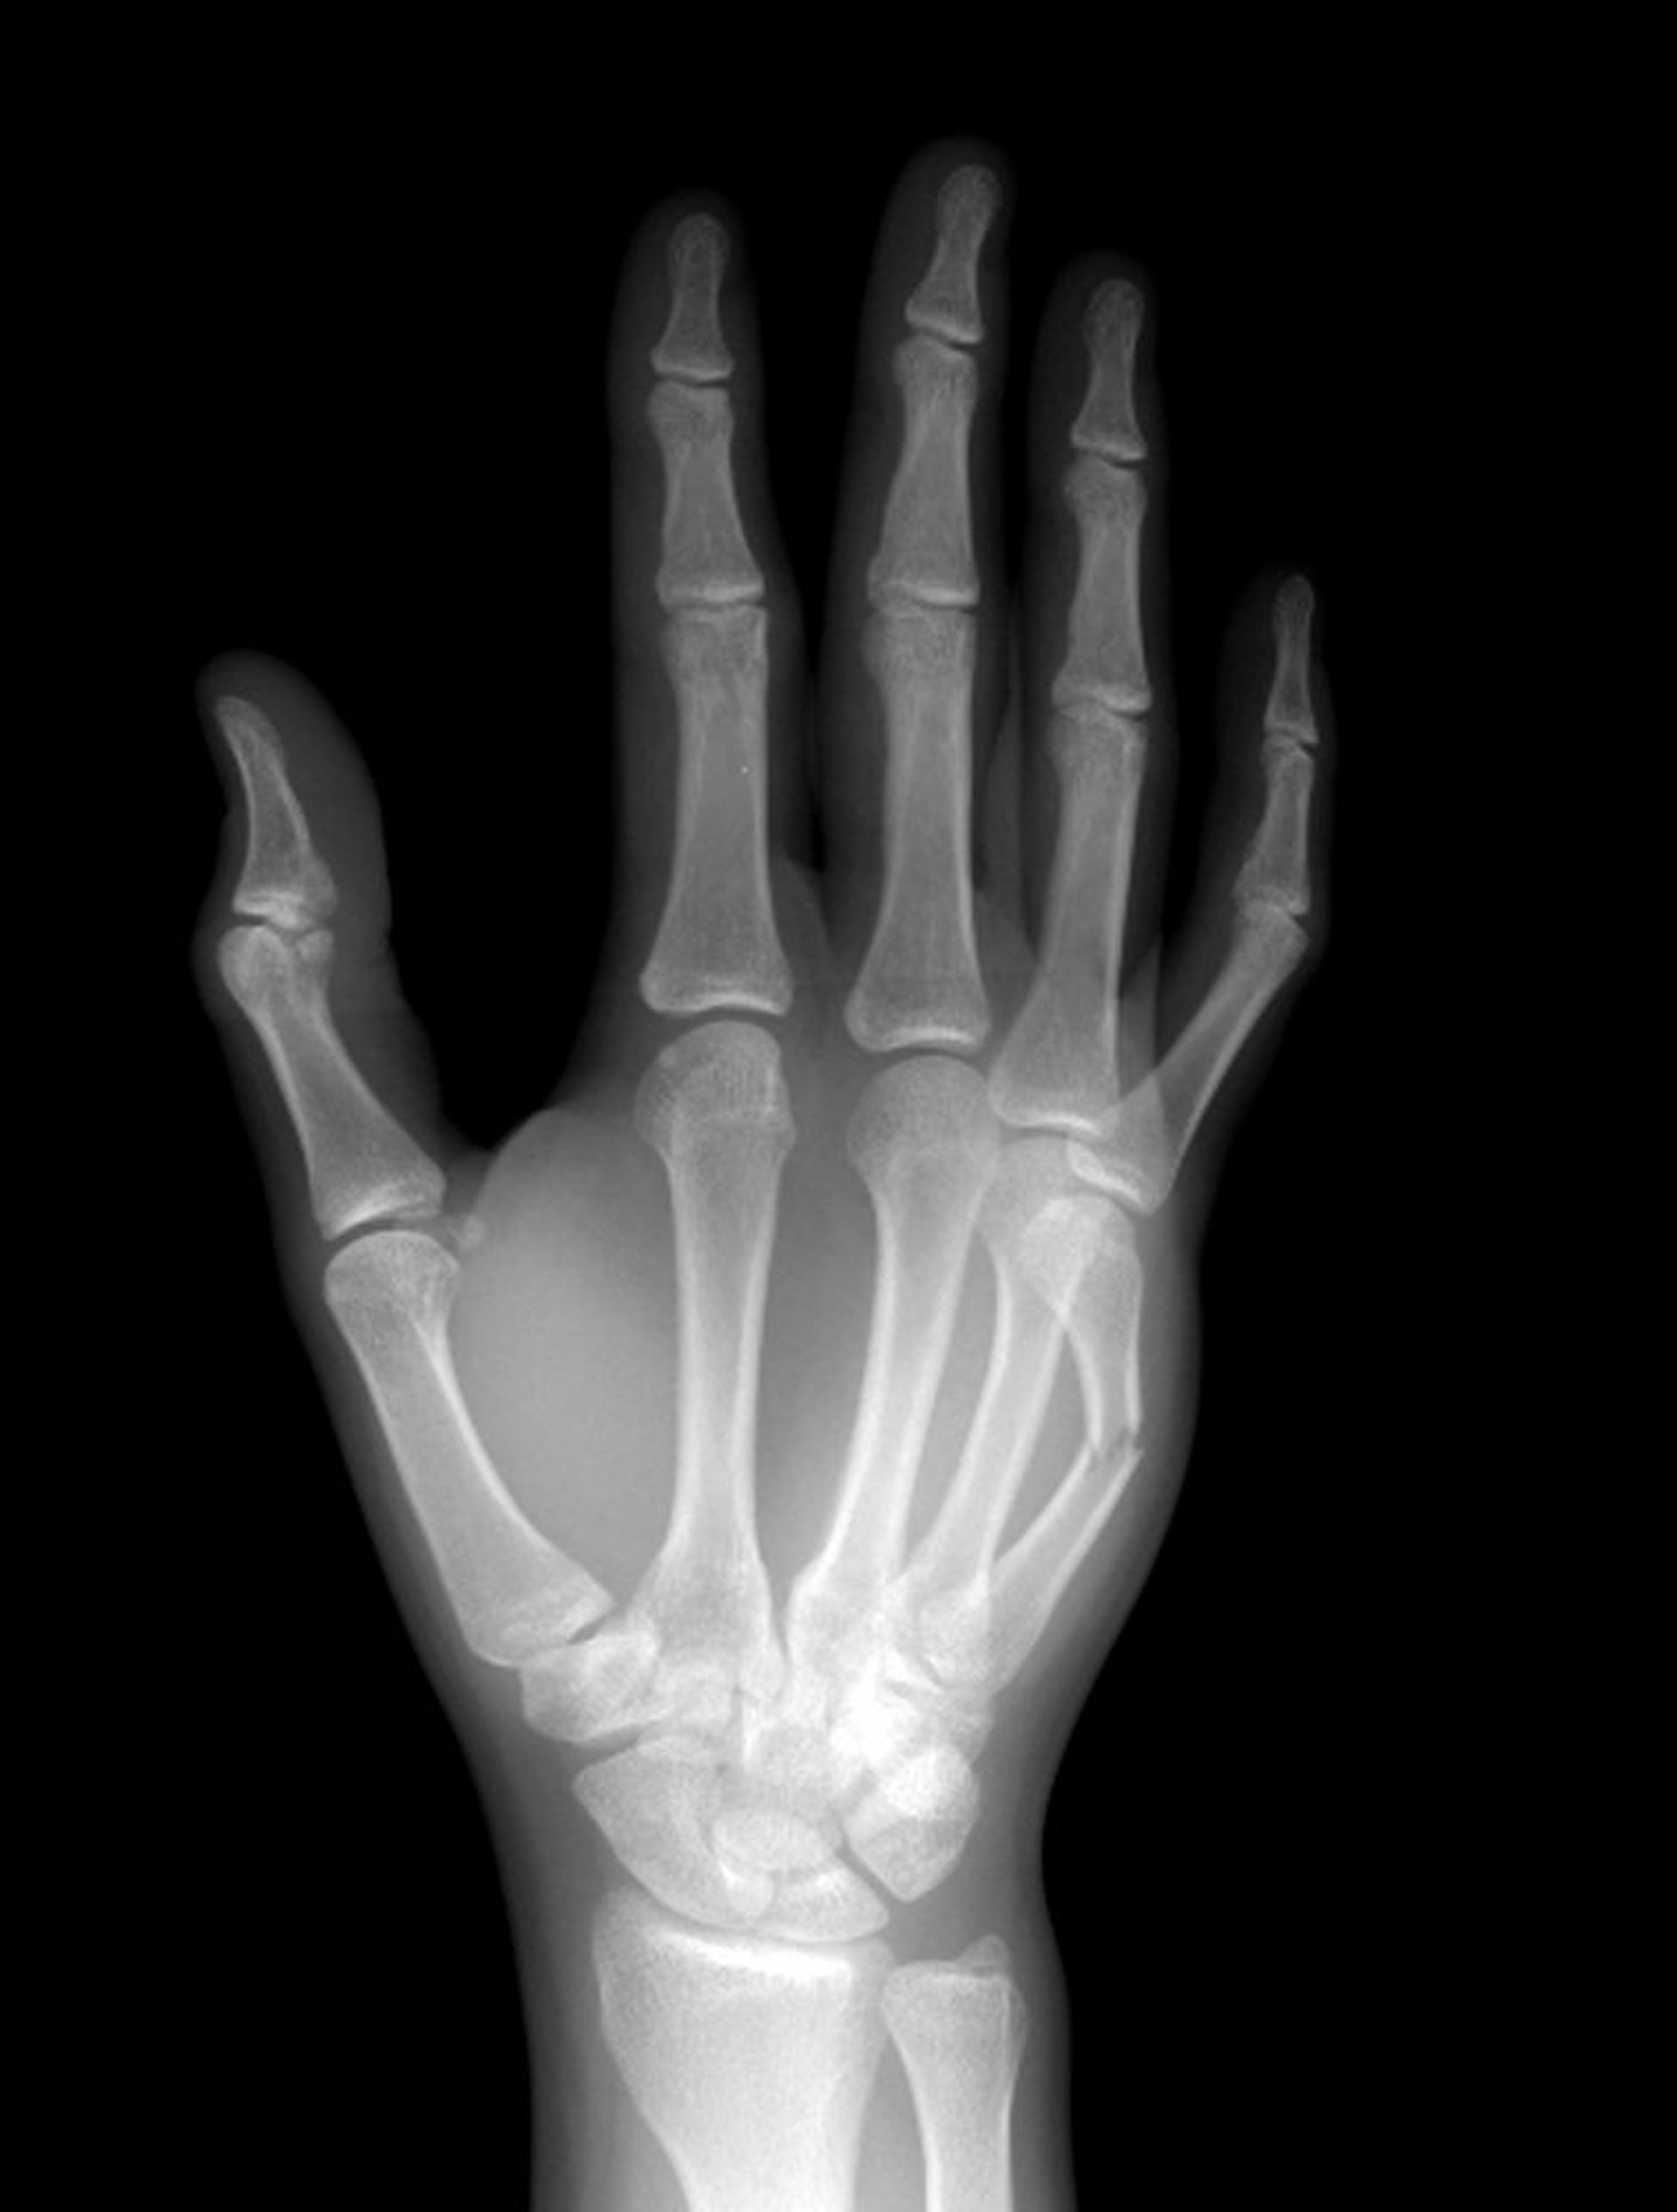

Fracture du col des métacarpiens

Le col du 5e os métacarpien est fracturé à mi-diaphyse.